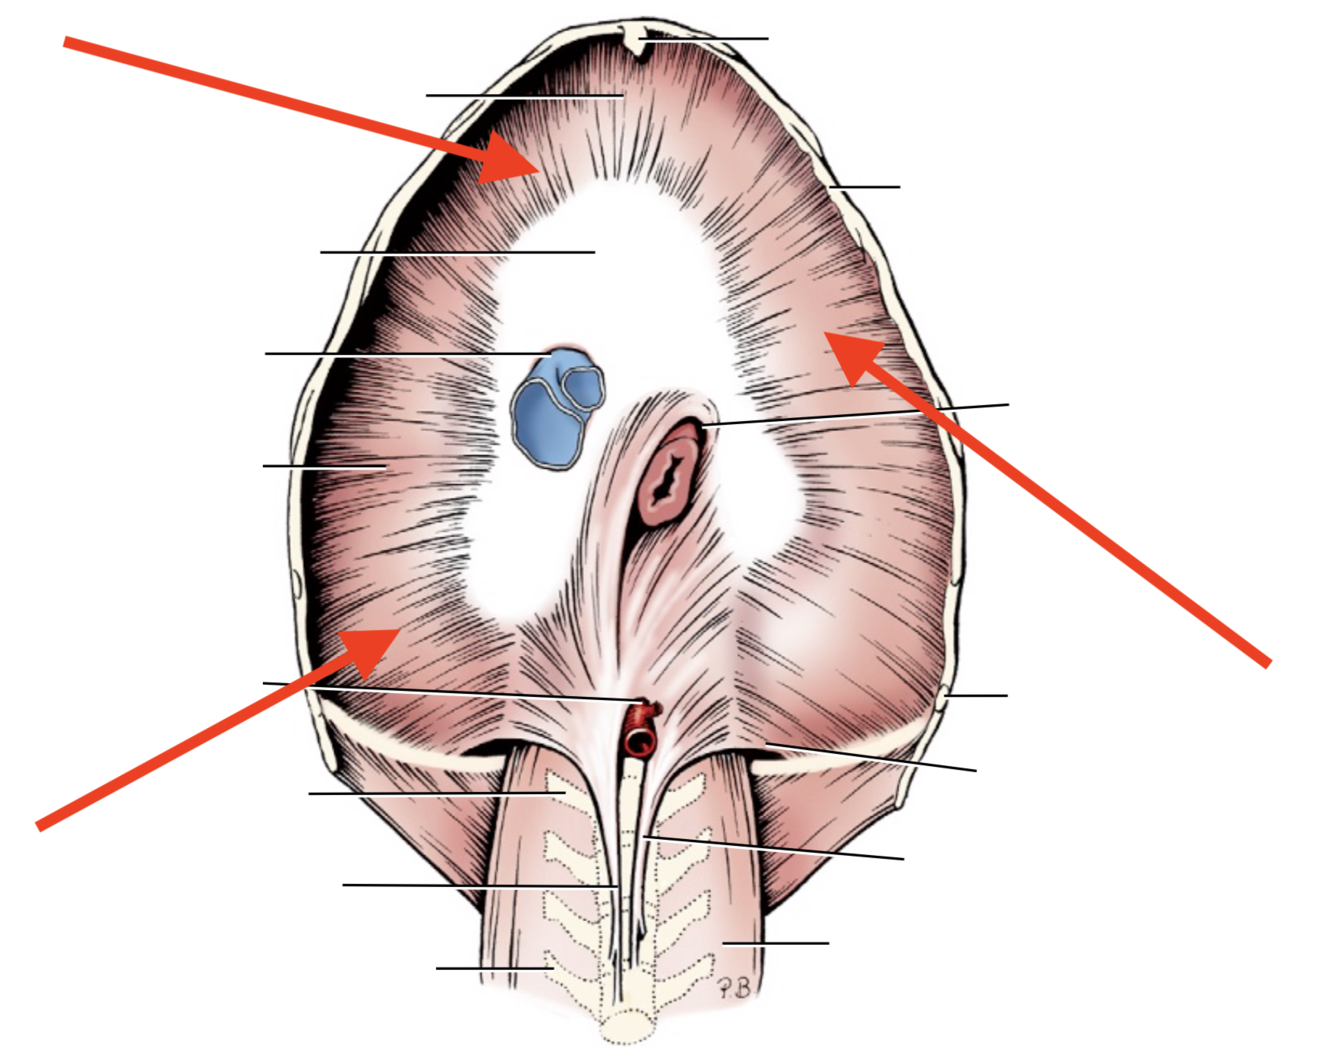

Name given to the most cranial part of the diaphragm.

Cupula Diaphragmatis

Q

Pars sternalis

Q

Foramen vena cavae

Q

Pars costalis

Q

Hiatus aorticus

Q

Arcus lumbocostalis

Q

Hiatus oesophagus

Q

Crus sinistrum

Q

Crus dextrum

Q

Centrum tendineum

Q

Corona muscularis